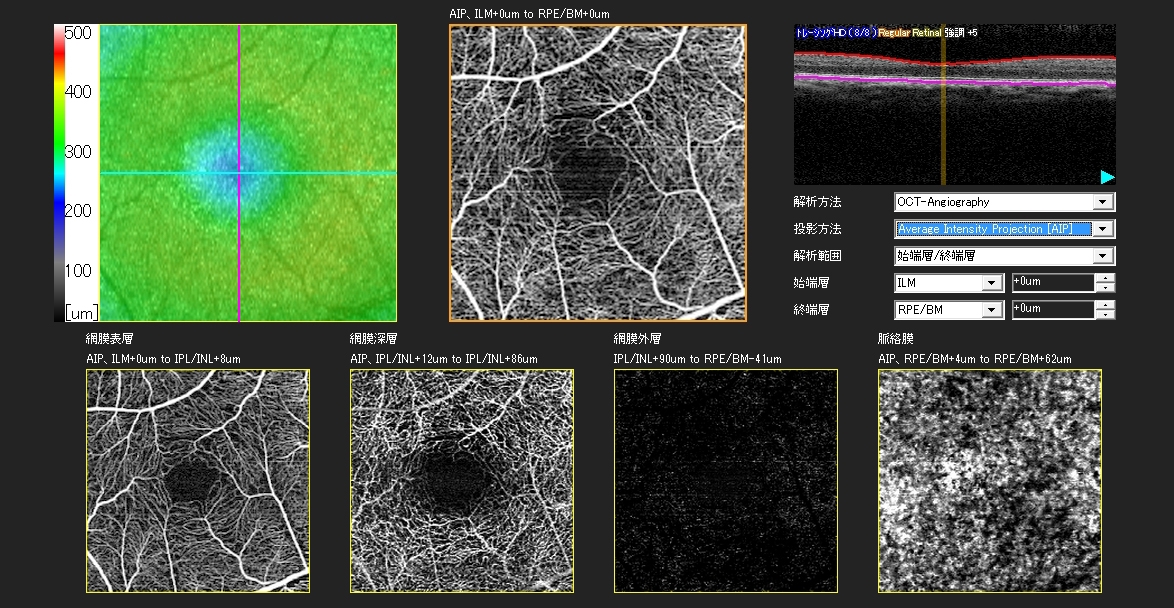

- CT-Angiographyにより、非侵襲で網膜毛細血管を各層別に観察可能(オプション)

任意設定により5種類(初期設定:網膜全層、表層、深層、外層、脈絡膜)のパノラマが同時に自動合成できます。

網膜表層 |

網膜深層 |

網膜外層 |

脈絡膜 |